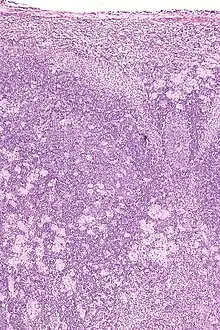

Lymph nodes affected by Toxoplasma have characteristic changes, including poorly demarcated reactive germinal centers, clusters of monocytoid B cells, and scattered epithelioid histiocytes.